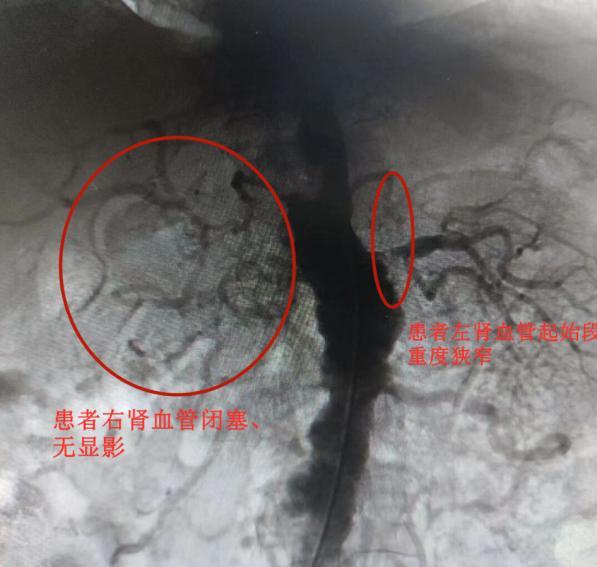

为尽快明确诊断,避免肾衰竭等致命风险,吴兴安立即为焉先生进行了造影探查,发现其右肾动脉已完全闭塞并萎缩,左肾动脉起始段狭窄达95%,十分危险。凭借丰富的同类病例手术经验,心血管介入团队当下决定通过右侧髂总动脉支架内真腔,将支架精准植入左肾动脉严重狭窄段,即时复通了左肾血管。

术后,患者左肾血管已复通。